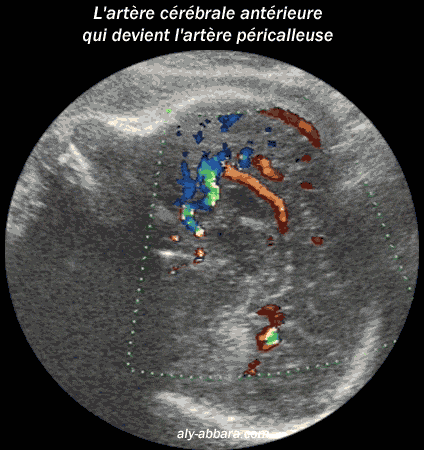

Coupe sagittale médiane du cerveau fœtal à 35 SA

L'artère cérébrale antérieure devenant l'artère péricalleuse